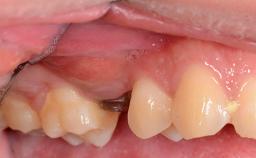

The patient presented with a failing tooth-supported fixed dental prosthesis with cantilever extension replacing the right maxillary central incisor. His chief presenting complaint was poor esthetics, in particular the dark discolored margin around the abutment tooth, the maxillary left central incisor. He reported a history of trauma at a young age, which necessitated the replacement of his maxillary right central incisor as well as root canal therapy of the adjacent left central incisor. The existing prosthesis had been in situ for over 20 years. The initial periapical radiograph displayed good proximal bone levels at the adjacent teeth and a wide incisive canal, which was a concern. The left central incisor presented a very wide root canal treatment with compromised radicular dentin thickness, which was a consideration in the decision between a new tooth-supported fixed dental prosthesis vs. an implant-supported prosthesis. After a lengthy discussion on the risks and benefits of both treatment options, the patient decided on a single-tooth implant replacement.

Soft Tissue Anatomy Intact Defective

Soft Tissue Contour and Volume Slightly compromised